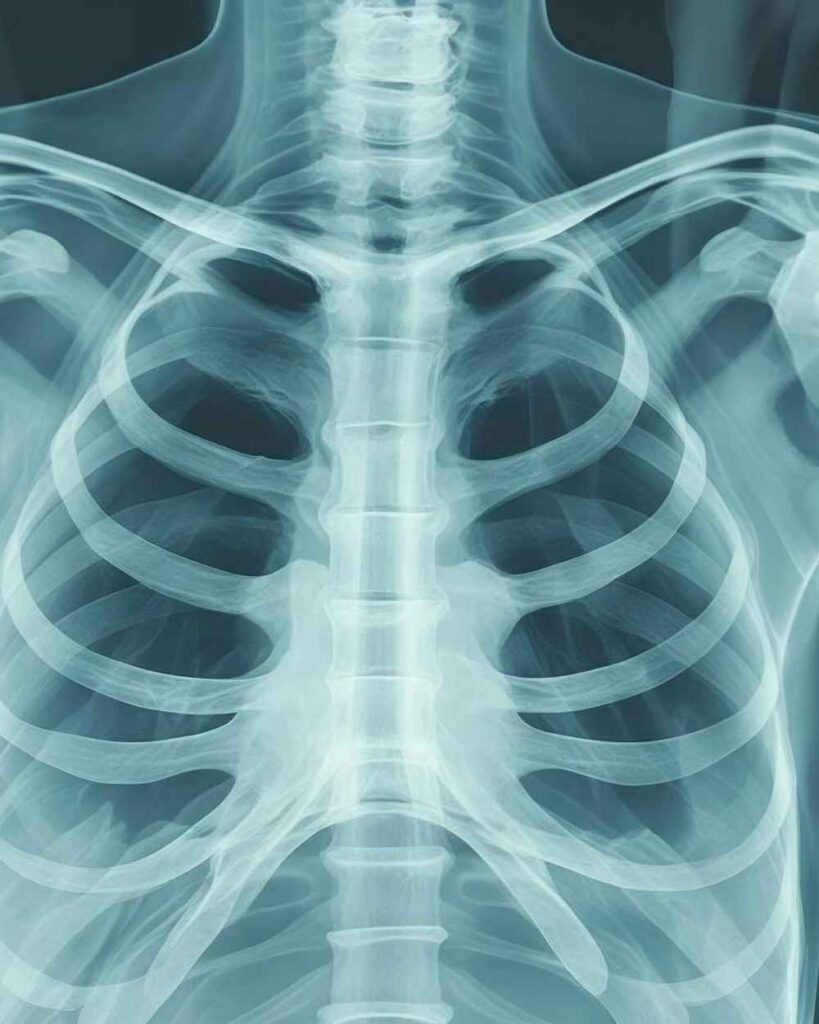

The Radiology department at Synergy Multispeciality Hospital plays a vital role in the early detection, diagnosis, and monitoring of various medical conditions. Equipped with modern imaging technology and handled by experienced radiologists, our department ensures accurate and timely results to support effective treatment decisions.

We offer a wide range of diagnostic imaging services including X-rays, ultrasound, and other advanced imaging techniques. These services help doctors understand internal conditions clearly and plan the right course of treatment. Our focus is on delivering high-quality imaging with safety, precision, and minimal discomfort to patients.

Our team follows strict safety protocols and uses advanced equipment to ensure reliable results while maintaining patient comfort. Whether it is a routine check-up or a detailed diagnostic evaluation, we are committed to providing fast, accurate, and dependable imaging services.

At Synergy Multispeciality Hospital, we believe that accurate diagnosis is the first step toward effective treatment. Our Radiology department supports all specialties with timely reports, helping doctors deliver the best possible care to every patient.